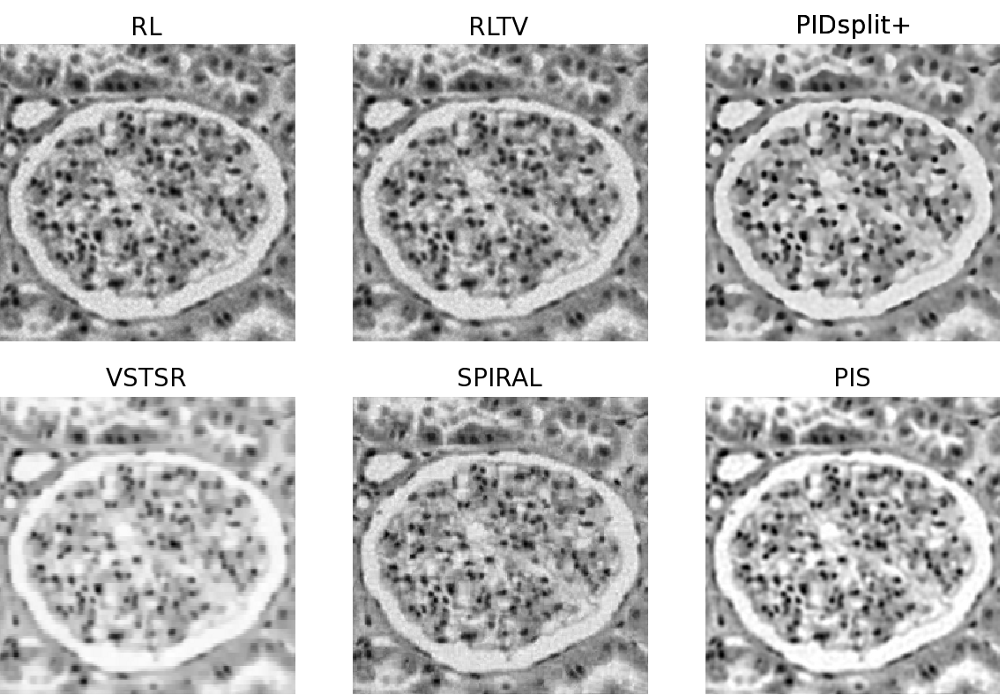

In this subsection, image reconstructions produced by the proposed and reference methods are tested using a microscopic image of glomerulus and the standard Shepp-Logan phantom, which are shown in Subplots A of Fig. 4 and Fig. 5, respectively. Similar to the case of sparse reconstruction, the images have been offset by a constant (background) value to give rise to different values of SNR. In particular, the value was adjusted to result in SNR equal to 32 (moderate noises) and 8 (strong noises). The original, blurred, and contaminated images of the glomerulus and Shepp-Logan phantom are summarized in Fig. 4 and Fig. 5 for all the tested values of and SNR.

For the case of glomerulus, the reconstructions obtained with the proposed and reference methods are summarized in Fig. 6 (for , SNR=32) and Fig.7 (for , SNR=8). Moreover, Fig. 8 and Fig. 9 depict the reconstructions of the Shepp-Logan phantom for the cases of , SNR=32 and , SNR=8, respectively. Analyzing these results, one can clearly see that, in all the above cases, the PIS algorithm yields reconstructions of superior quality (in terms of the resolution and contrast gain), as compared to the reference methods. This observation is further supported by the quantitative measures of Tables III and IV, which compare the estimation results in terms of the NMSE, SSIM index, and the number of iterations. As evidenced by the tables, the PIS method produces the lowest NMSE and the largest SSIM index among all the methods under comparison. As to the number of iterations required by PIS, one can see (with a reference to Table II) that the method has a computational complexity either comparable or lower than that of the reference methods.